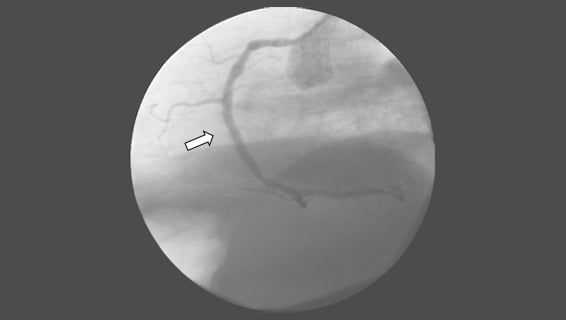

• If the patient arrives early to open the blocked coronary arteries, first emergency coronary angioplasty (balloon) is performed and after angioplasty, a steel cage called a stent is placed to keep the coronary artery open.